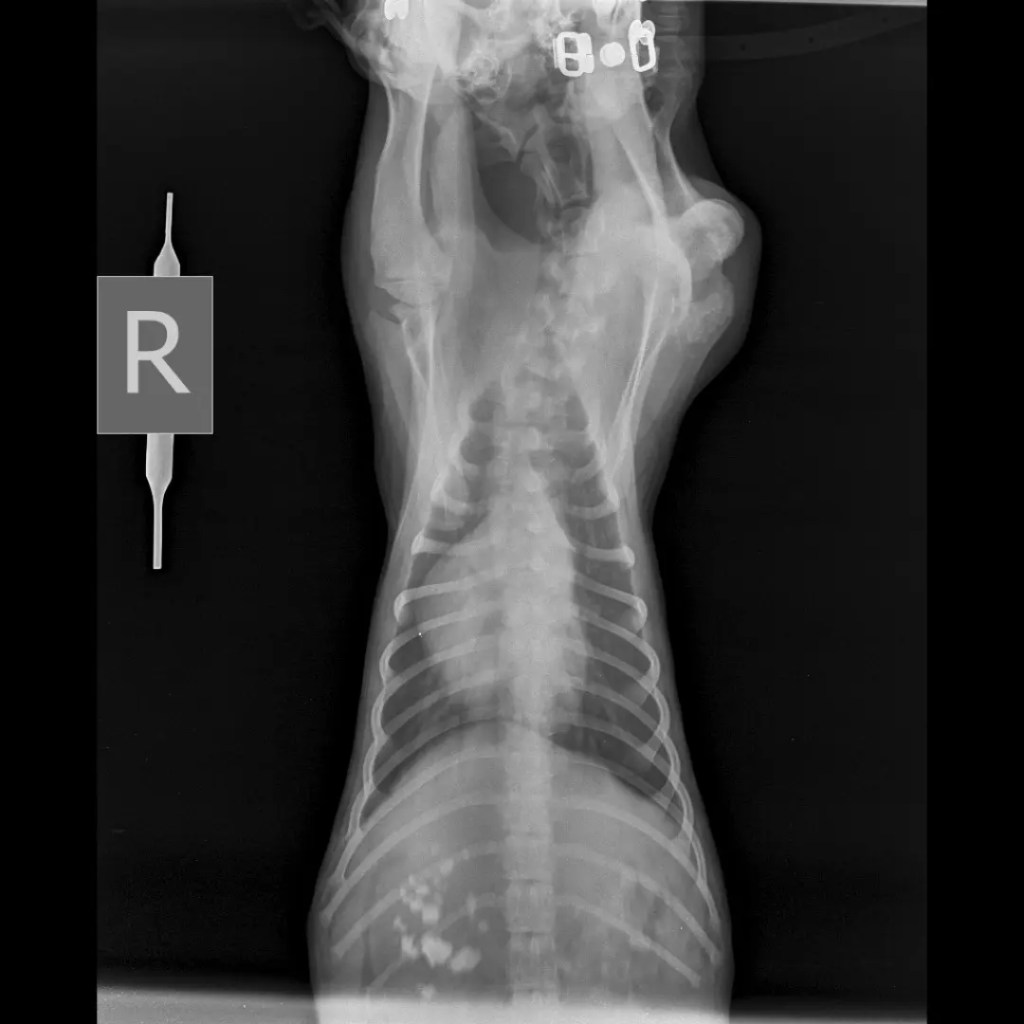

He’s frisky and doesn’t allow to touch him much so we got him caught and sent him to the vet for x-rays. The x-rays revealed that sure enough there was an injury but now with time it’s fused in such a way that he has a slight dislocated look and limp but is not in pain.

We got his blood work done and he has been detected with tick fever! Had to send him to the shelter because he’s a no touchy touchy boy and Medicating him onsite is going to be a herculean task since it’s antibiotics and he can’t even miss a day.. he will be well looked after, medicated and fed well too. Can’t wait for him to recover and come back home as a healthy gorgeous shiny black pup ๐ค ๐พ